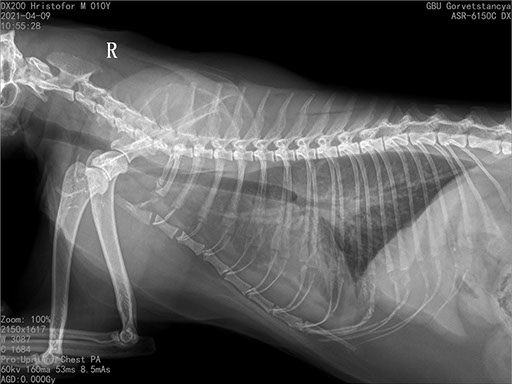

Цифровая рентгеновская установка ASR-6150C поставляется с мобильным столом пациента и комплектом рентгенопрозрачных анатомических ложементов всех размеров, видов и пород домашних животных.